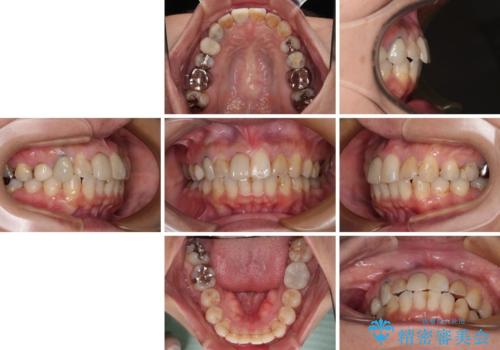

【モニター】処置歯の多い歯列 インビザラインでデコボコを整える

- 上下前歯のデコボコを気にして来院された患者様です。

歯列としては、ワイヤー装置でもインビザラインでも、どちらでも対応可能でしたが、処置されている歯が多く、ワイヤー装置を装着するためには処置歯のやり直しが必要な状態でした。

インビザラインでもアタッチメントを装着できないという同様のデメリットがありますが、比較的矯正治療を行いやすい歯列であったので、インビザラインによる矯正治療を行うこととしました。

術中や仕上がりに特に大きなトラブルはなく、スムーズに治療を終えることができました。